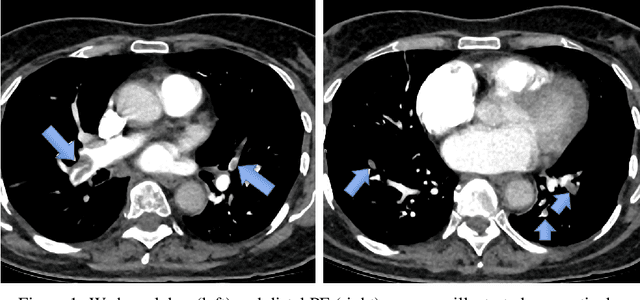

Abstract:Pulmonary Embolism (PE) is a serious cardiovascular condition that remains a leading cause of mortality and critical illness, underscoring the need for enhanced diagnostic strategies. Conventional clinical methods have limited success in predicting 30-day in-hospital mortality of PE patients. In this study, we present a new algorithm, called PEP-Net, for 30-day mortality prediction of PE patients based on the initial imaging data (CT) that opportunistically integrates a 3D Residual Network (3DResNet) with Extreme Gradient Boosting (XGBoost) algorithm with patient level binary labels without annotations of the emboli and its extent. Our proposed system offers a comprehensive prediction strategy by handling class imbalance problems, reducing overfitting via regularization, and reducing the prediction variance for more stable predictions. PEP-Net was tested in a cohort of 193 volumetric CT scans diagnosed with Acute PE, and it demonstrated a superior performance by significantly outperforming baseline models (76-78\%) with an accuracy of 94.5\% (+/-0.3) and 94.0\% (+/-0.7) when the input image is either lung region (Lung-ROI) or heart region (Cardiac-ROI). Our results advance PE prognostics by using only initial imaging data, setting a new benchmark in the field. While purely deep learning models have become the go-to for many medical classification (diagnostic) tasks, combined ResNet and XGBoost models herein outperform sole deep learning models due to a potential reason for having lack of enough data.